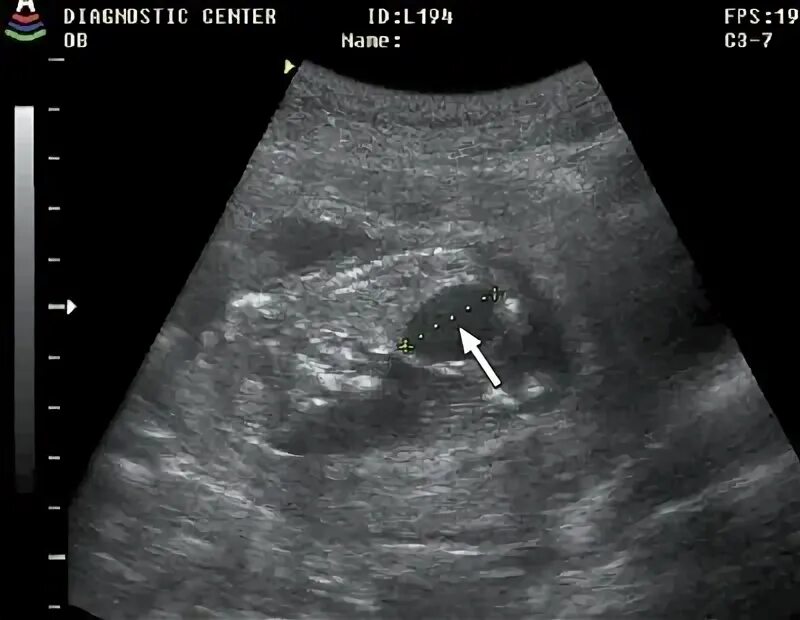

На какой недели можно увидеть плод